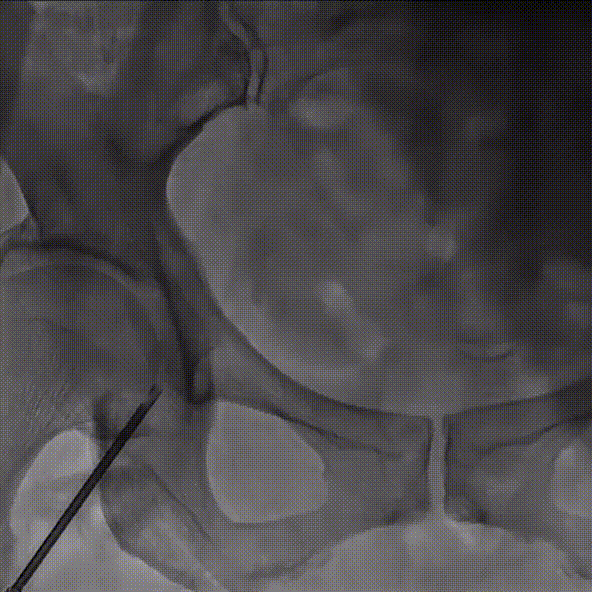

4、术后即刻超声,峰值流速:1.6m/s;平均压差:11mmHg ,仅微量瓣周漏

术后超声